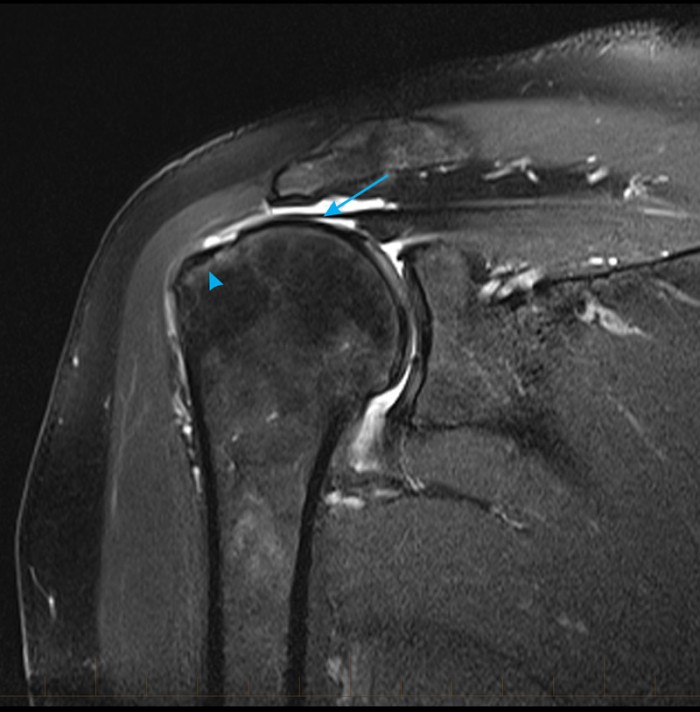

Full Thickness Supraspinatus Tear Mri What Is A Full Thickness Tear Of A Tendon Stage 0 is an intact. It happens when the injury to your rotator cuff muscle. types of torn rotator cuffs include: a classification system described by harryman et al. Is based on the size and number of tendons involved. front (left) and side (right) views of the tendons that form the rotator cuff. With an incomplete or. What Is A Full Thickness Tear Of A Tendon.